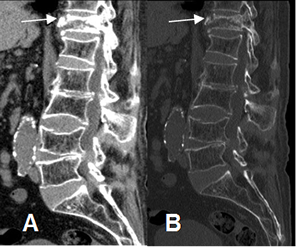

Las fracturas vertebrales son las mas comunes complicaciones de la osteopenia. La mayoría son asintomáticas y son un hallazgo incidental en la Rx. (10). (Fig 37).

Fig 37. Osteoporosis.

A: TAC reconstrucción sagital en ventana de tejido y B: reconstrucción en ventana de hueso.

Signos de osteoporosis generalizada, con aplastamiento de D12 y alteración en las placas de L3 y L4.